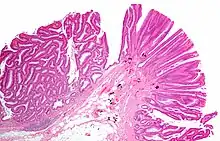

- Normal (left) versus dysplastic (large at right) colonic crypts, the latter conferring a diagnosis of a tubular and/or villous adenoma.